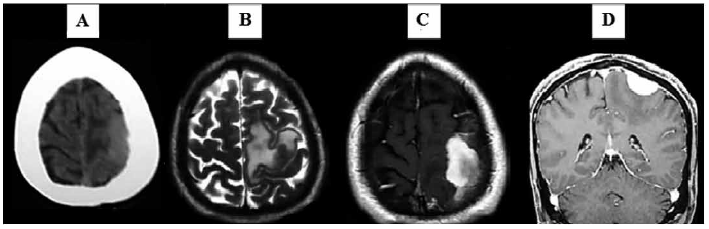

En la tomografía cerebral sin contraste se evidenció una lesión hiperdensa fronto-parietal izquierda con edema cerebral e hiperostosis asociada. La resonancia magnética cerebral con contraste confirmó la presencia de un proceso expansivo extra-axial fronto-parietal izquierdo con captación homogénea de contraste (Figura 1). Con estos resultados, el diagnóstico presuntivo prequirúrgico fue el de una lesión neoplásica, dependiente de la duramadre, sugestiva de meningioma de la convexidad.

(A) Tomografía sin contraste corte axial: Lesión extra-axial, hiperdensa (en relación con parénquima cerebral) en región fronto-parietal izquierda, con edema asociado e hiperostosis en tabla interna craneal adyacente a lesión .(B) RMN T2 axial: Lesión a nivel fronto-parietal izquierda con edema asociado, nexo a giro precentral (en relación al “omega invertido” o área motora de la mano) y giro poscentral (área somatosensorial primaria) que no involucra la pared del seno sagital superior.(C) RMN T1C axial con contraste: Lesión captadora de contraste (gadolinio), bien delimitada, de bordes discretamente irregulares y de centro denso. (D) RMN T1C coronal con contraste: Lesión extra-axial con “cola dural” o “cola de ratón”, a ambos lados de su parte central. La captación de contraste por la lesión es homogénea. El edema vasogénico, que incrementa el efecto de masa, lateraliza el falx del cerebro.

Las imágenes de tomografía computarizada y de resonancia magnética del encéfalo permitieron identificar una masa extra-axial con edema cortico-subcortical y captación de contraste a nivel fronto-parietal izquierdo. Al respecto, los hallazgos en las imágenes del encéfalo describen a la ERD intracraneal simulando cualquier lesión extra-axial de la convexidad; aunque algunos no describen el realce dural (“cola dural”) [7]. Sin embargo, este hallazgo fue evidente en el presente caso (Figura 1D). En similitud con otras publicaciones, se identifican a la ERD intracraneal como una entidad que en las neuroimágenes “imita” al meningioma intracraneal [7-9]. La Tabla 1 resume las características imagenológicas del meningioma y la ERD intracraneal [7-14].